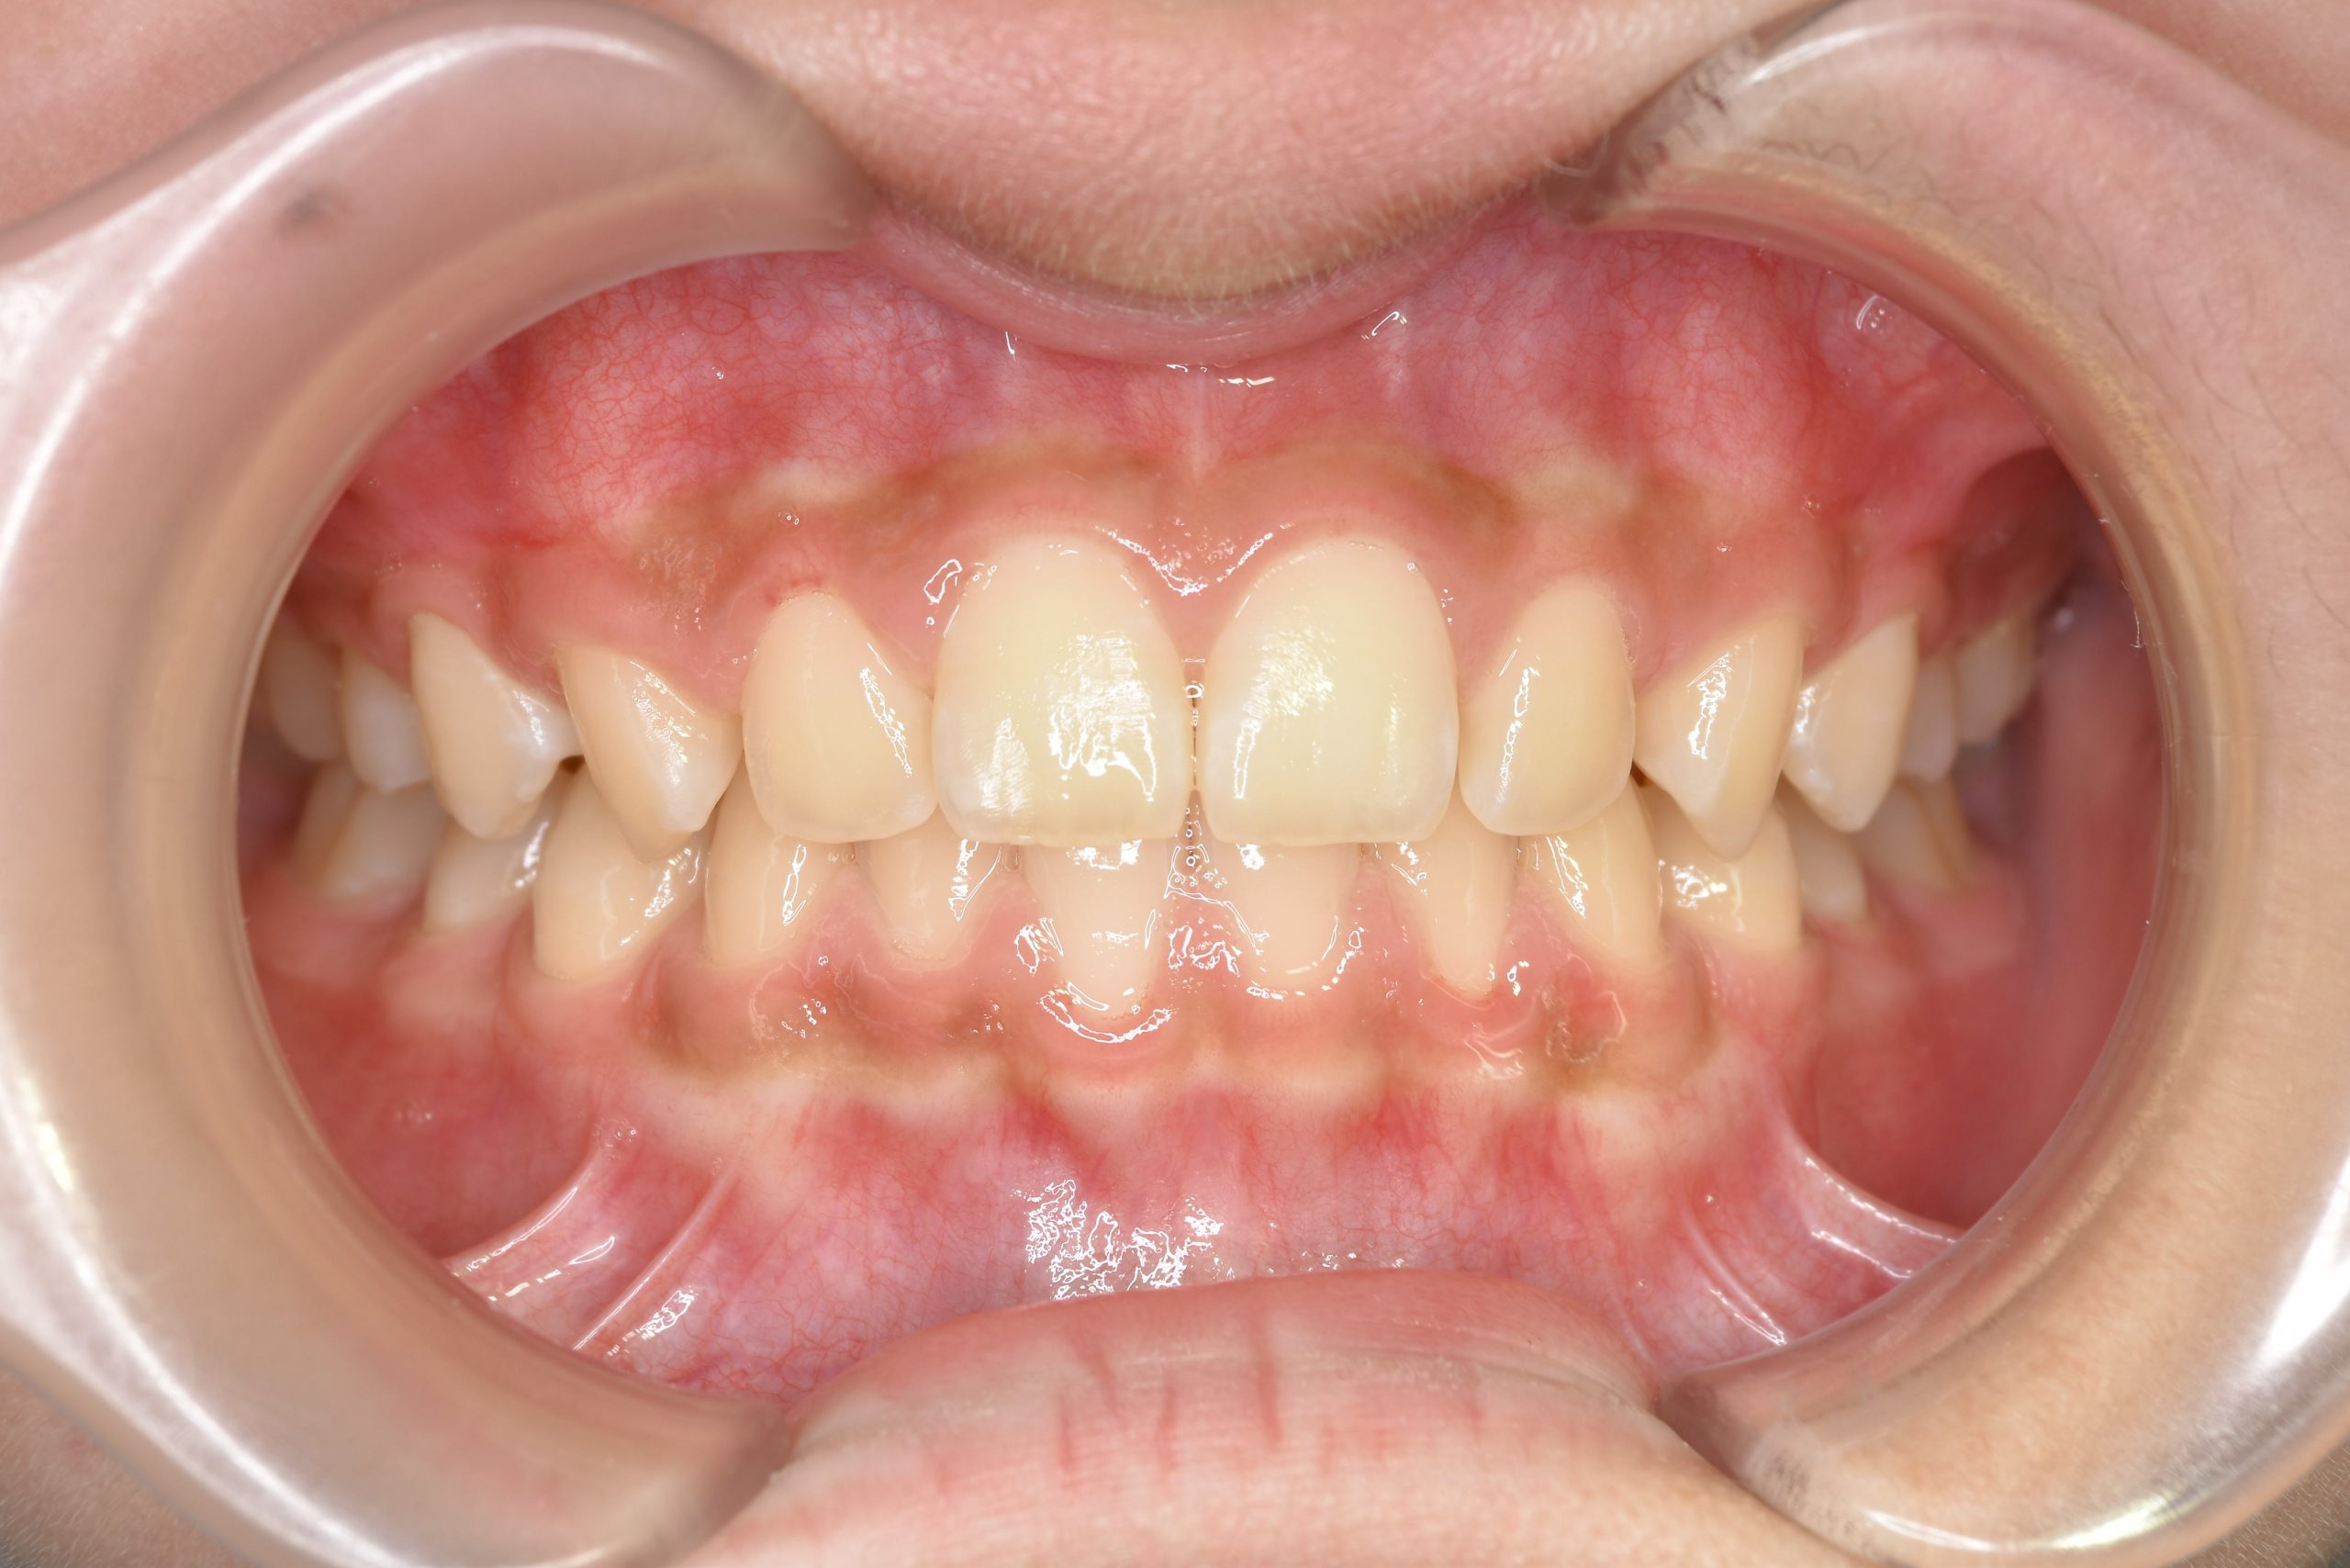

ビフォー

全顎ワイヤー矯正 症例_108

主訴 受け口|前歯がかみ合わない|顔貌

施術内容 小児矯正1期治療

治癒期間 3年11ヶ月間

費用 498,960円(税込)